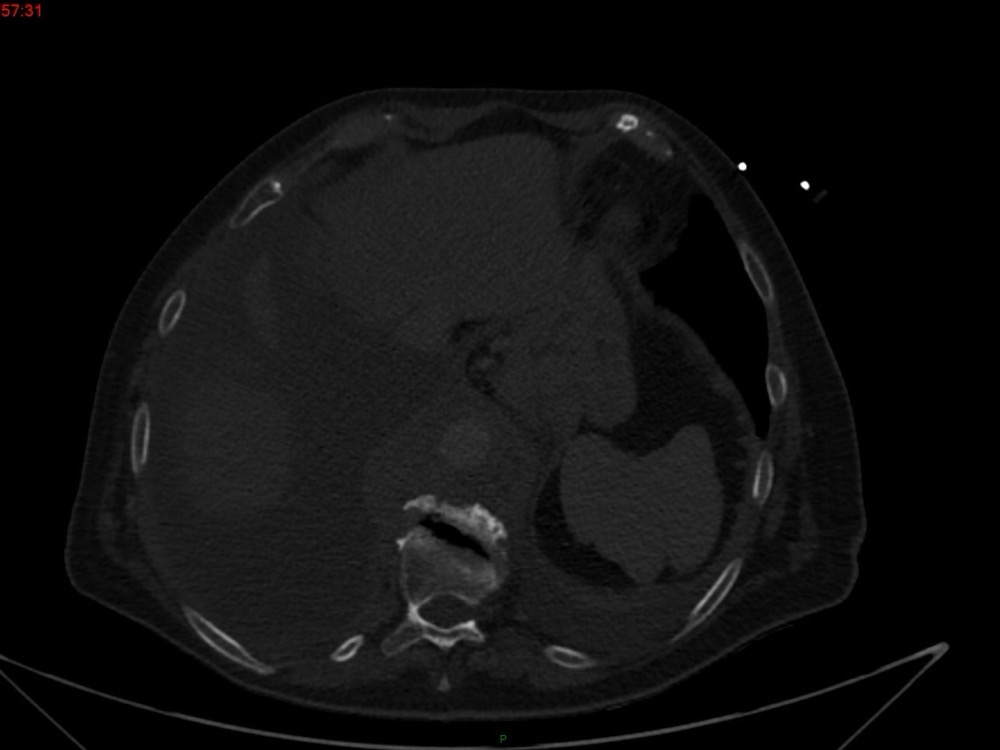

Marie Pauline Talabard 11/01/2023